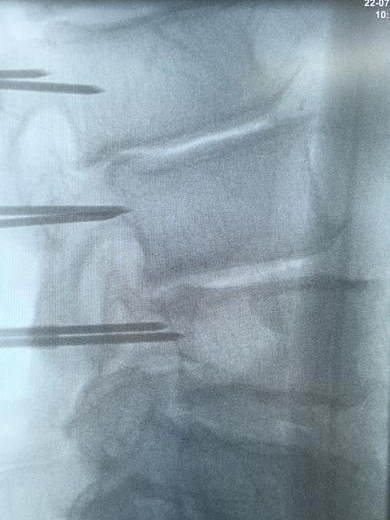

使用术中个体化导向模板

提高置钉安全性及成功率

陈勇主任团队顺利为患者置入椎弓根螺钉。术后患者腰腿痛症状较术前明显缓解,肢体活动无障碍,术后3天即在脊柱支具外固定的辅助下下地行走,术后第7天患者恢复情况良好,顺利出院。

▲术中椎弓根螺钉精准置入